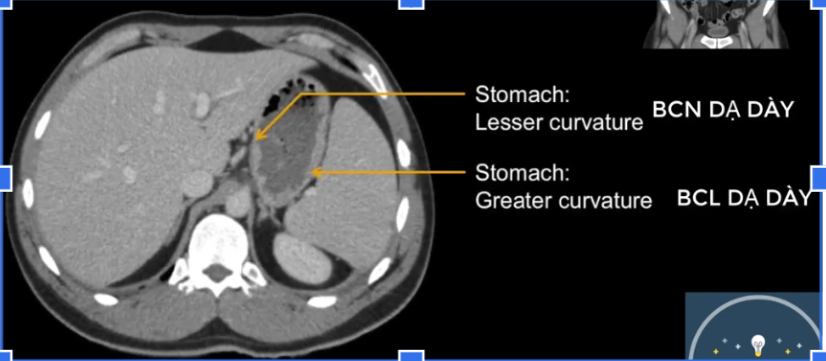

cq trong hình ?